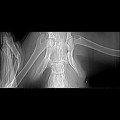

CT - lebka